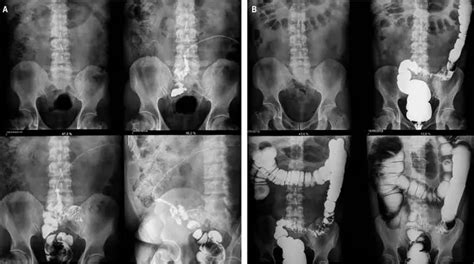

A fin de averiguar el origen de la lesión, se realiza una fistulografía empleando un cono de gutapercha dirigido hacia la línea media.

Imagen de la fistulografía. El cono de gutapercha se dirige a la línea media. Se nota reabsorción ósea interproximal en el tercio cervical.